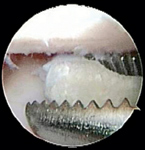

Otras pruebas de diagnóstico para ayudar a diferenciar las causas de la patología del codo son la artrocentesis, las imágenes y la artroscopia. Las radiografías son de poco valor en la identificación del fragmento o la línea de separación vista con el clásico FMCP o TFMCP (Foto 1). Las técnicas más avanzadas de imágenes como la tomografía computarizada, la resonancia magnética y la artroscopia pueden ayudar a confirmar la condición. La evaluación artroscópica de la articulación del codo tiene las siguientes ventajas: la observación directa y el aumento de todas las principales estructuras intra-articulares, la evaluación dinámica de los tejidos durante los ejercicios de rango de movimiento y la palpación de los tejidos intra-articulares con instrumentos para artroscopía. En consecuencia, la exploración artroscópica definitivamente puede ayudar a diagnosticar TFMCP cuando se observa un fragmento o fisura de cartílago (Foto 2). En un pequeño porcentaje de casos, las imágenes avanzadas (tomografía computarizada, resonancia magnética) indican la fragmentación de la coronoides no vista con la artroscopia. En tales casos, se cree que las microfracturas están dentro del hueso coronoides por debajo de la superficie del cartílago.

Dependiendo de la severidad de la enfermedad, el tratamiento artroscópico puede incluir la remoción del fragmento (Foto 3), el desbridamiento de los tejidos enfermos, la creación de un acceso vascular mediante artroplastia de abrasión, microfractura y ostectomía subtotal de coronoides. En comparación con una artrotomía quirúrgica tradicional, la artroscopía permite una mejor visualización de estructuras en la articulación, traumatismos en los tejidos menos blandos, así como menores tiempos de hospitalización y cirugía, disminución del riesgo de infección y menor tiempo de recuperación.